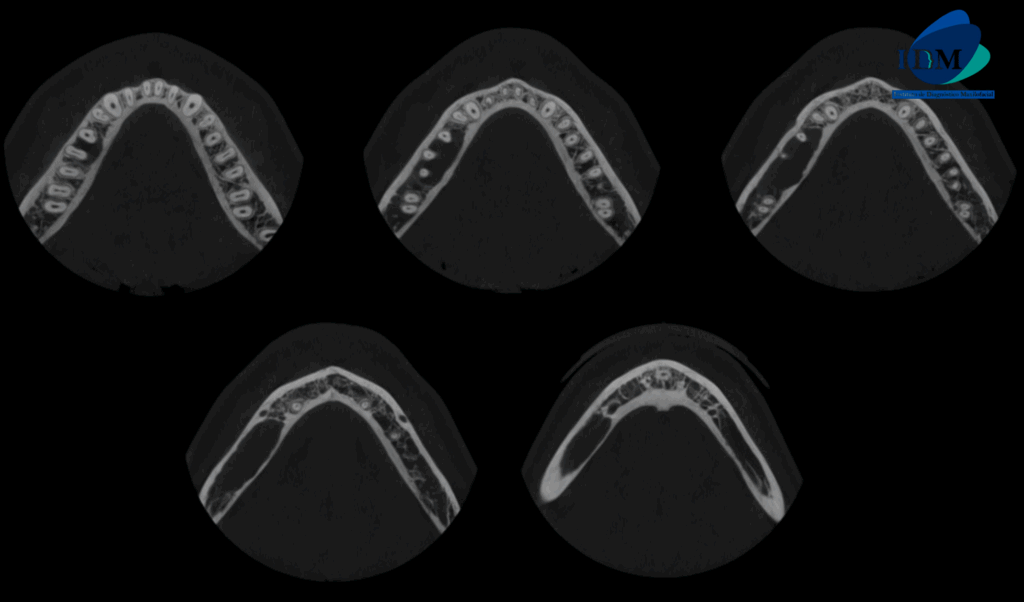

CORTES AXIALES